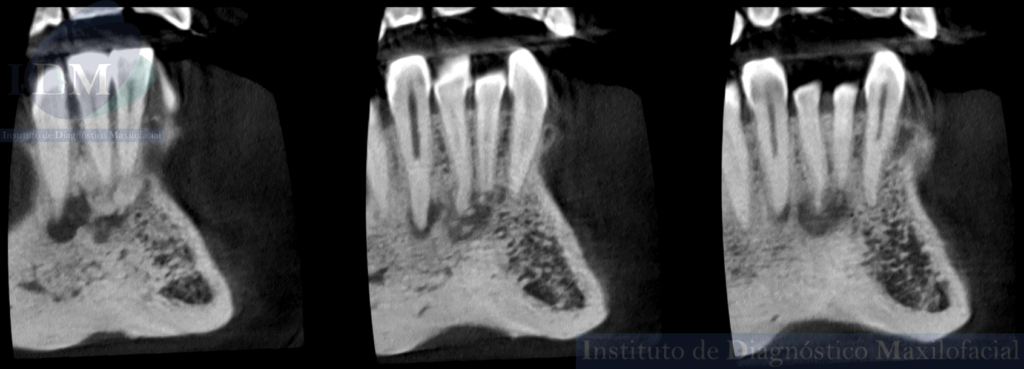

Así mismo en la tomografía volumétrica de haz cónico de campo reducido evidenciamos que dichas imágenes mixtas se encuentran comprometiendo zona a pical de la pieza 41 y 42 con un aumento de la densidad ósea adyacente. Siendo la imagen hipodensa a nivel a pical de la pieza 43 una probable lesión apical.

CORTES TANGENCIALES